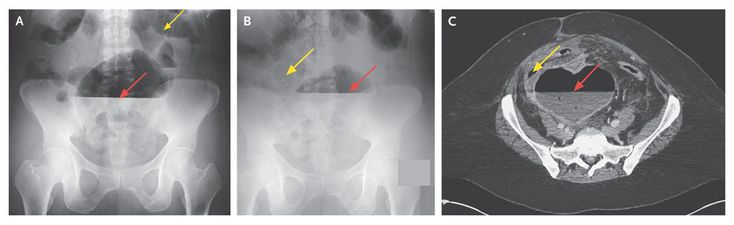

A 44-year-old woman with a history of Crohn's disease presented with a 1-week history of progressive abdominal distention, nausea, and feculent vomiting and reported having lost 13.6 kg during the preceding 6 months. She had undergone ileocecostomy 20 years earlier and had been treated with infliximab for 10 years before the current presentation. On presentation, the patient was afebrile and normotensive. An abdominal examination revealed normal bowel sounds and infraumbilical tenderness, without rebound. Laboratory tests showed a normal leukocyte count, but the erythrocyte sedimentation rate and the level of C-reactive protein were elevated, at 67 mm per hour and 121 mg per liter, respectively. Abdominal radiographs showed gaseous distention of multiple small bowel loops (Panels A and B, yellow arrows) and a larger air collection in the middle-to-lower abdomen, where a long air–fluid level (red arrows) could be seen on upright images. Computed tomographic enterography was performed to further investigate these findings and revealed a mesenteric abscess measuring 9 cm by 10 cm by 18 cm that was filled with air and fluid (Panel C, red arrow) and was displacing small bowel loops (yellow arrow). The patient underwent percutaneous drainage and was given antibiotics intravenously and ultimately underwent complete proctocolectomy with end ileostomy. After surgery, biologic therapy was reinitiated, with good clinical results.